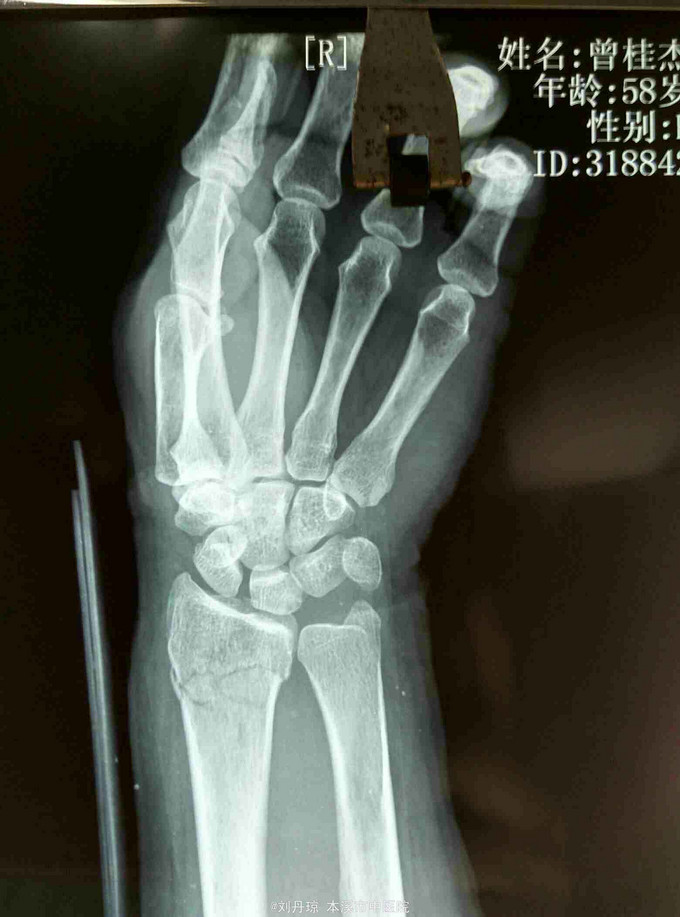

主诉:左腕刺痛,活动受限3小时。 病史: 患者3小时前不慎摔伤腕,伤后左腕刺痛,活动受限。遂来我院门诊求治。

诊断: 左colles骨折 治疗:手法整复,夹板固定,中药外用,接骨续筋中药口服。

随访|年。摔倒时腕关节极度背伸,使前臂旋前的扭力向前运动,导致此型骨折。colles 骨折占前臂骨折的75%,多见于中老年女性。colles骨折是最常见的骨折。典型表现为餐叉状畸形。主要包括然后远端向背侧移位和倾斜,桡偏,桡骨短缩,骨折常涉及桡腕关节和下尺桡关节。尺骨茎突骨折也是常见的合并损伤。